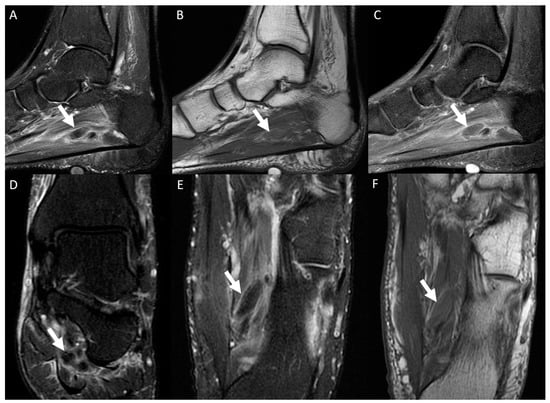

| Muscular edema | 112/130 (86.2%) | 70/86 (81.4%) | 42/44 (95.5%) | p = 0.028 |

| Intravascular signal characteristics on T2-weighted images | High 108/130 (83.1%) | High 68/86 (79.1%) | High 40/44 (90.9%) | p = 0.044 |

| Perivascular edema | 130/130 (100%) | 86/86 (100%) | 44/44 (100%) | p > 0.999 |

| Perivascular enhancement | 130/130 (100%) | 86/86 (100%) | 44/44 (100%) | p > 0.999 |

| Intravenous filling defect | 127/130 (97.7%) | 84/86 (97.7%) | 43/44 (97.7%) | p > 0.999 |

| Venous ectasia | 130/130 (100%) | 86/86 (100%) | 44/44 (100%) | p > 0.999 |